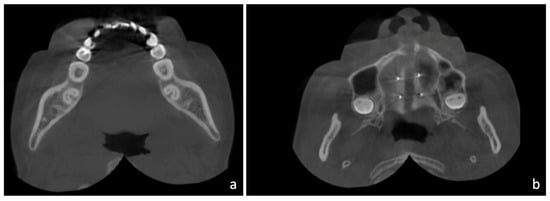

- Angelieri, F.; Cevidanes, L.H.; Franchi, L.; Goncalves, J.R.; Benavides, E.; McNamara, J.A., Jr. Midpalatal suture maturation: Classification method for individual assessment before rapid maxillary expansion. Am. J. Orthod. Dentofac. Orthop. 2013, 144, 759–769. [Google Scholar] [CrossRef] [Green Version]

- Cantarella, D.; Dominguez-Mompell, R.; Mallya, S.M.; Moschik, C.; Pan, H.C.; Miller, J.; Moon, W. Changes in the midpalatal and pterygopalatine sutures induced by micro-implant-supported skeletal expander, analyzed with a novel 3D method based on CBCT imaging. Prog. Orthod. 2017, 18, 34. [Google Scholar] [CrossRef]